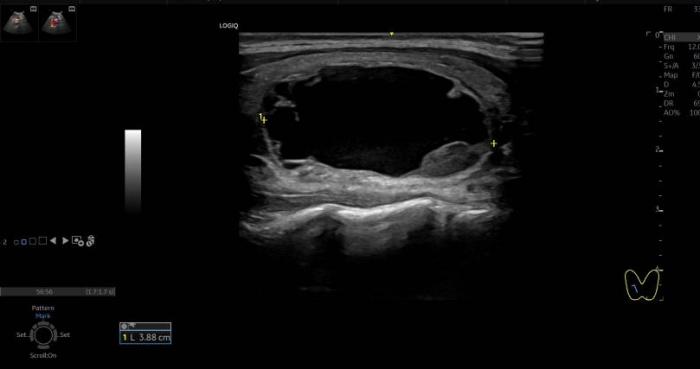

家住郴州市的小明(化名)近来摸到颈部一肿块,明显凸出,影响美观,在湘南学院附属医院超声医学科检查发现是甲状腺囊肿。罗红缨介绍,甲状腺囊肿是指在甲状腺中带有液体的囊状物。包括甲状腺真性囊肿、滤泡囊肿以及腺瘤囊性变(以囊性为主含少量实性的结节)等。“甲状腺囊肿的诊断很简单,做个甲状腺彩超,就一目了然了。”罗红缨说,“目前甲状腺囊肿的治疗方法有传统外科手术和超声引导下硬化治疗术两种。相比之下,超声引导下硬化治疗具有精准治疗、创伤小,出血少、恢复快、安全可靠、无疤痕,可以多次治疗等诸多优势。”

经过一系列检查后,医务人员为小明实施了硬化治疗,在超声引导下,抽掉囊液并将硬化剂注入囊肿内,破坏囊壁,缩小囊肿,在皮肤仅留下一针眼大小的伤口,脖子肿物明显变小,小明对治疗效果特别满意。